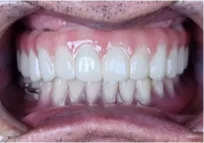

풀아치 임플란트 수술후 (2024.02.29)

최종 보철물 연결 (2024.02.29)